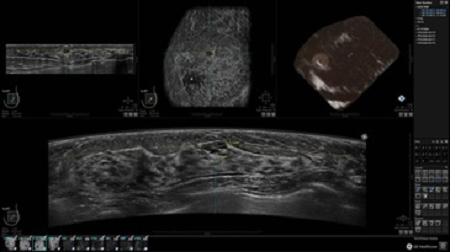

GE INVENIA ABUS – это современный УЗИ аппарат, который создан для точной и эффективной диагностики сканирования с высокой плотностью молочных желез. Выявляемость патологий раковых и предраковых стадий заболевания составляет 55%, что в конечном счете позволяет ставить врачу точные и своевременные диагнозы. Традиционные методы использования маммографии не показывают такой выявляемости, ограничиваясь лишь 3-38%.

УЗИ-аппарат GE INVENIA ABUS позволяет проводить максимально операторонезависимые процедуры, что значительно снижает риск неправильной постановки диагноза и сопутствующие издержки на обработку информации. Система готовит отчет в течение 3-х минут после сканирования, это безусловное преимущество по сравнению с обычным УЗИ сканером.

• Получение объемных 3D изображений с возможностью покадрового просмотра

• Отображение объемных 3D ультразвуковых изображений, которые состоят из традиционных поперечных и воссозданных коронарных и сагиттальных проекций

• Возможность отображения полного 3D изображения

• Многооконный просмотр: 4 - 12 изображений

• Стандартизованная ориентация изображения: «толстый срез» в коронарной плоскости; поперечная; сагиттальная плоскость; радиальный и антирадиальный поворот изображения; просмотр исключительно области интереса

• Программное обеспечение Invenia ABUS Review Software для рабочей станции